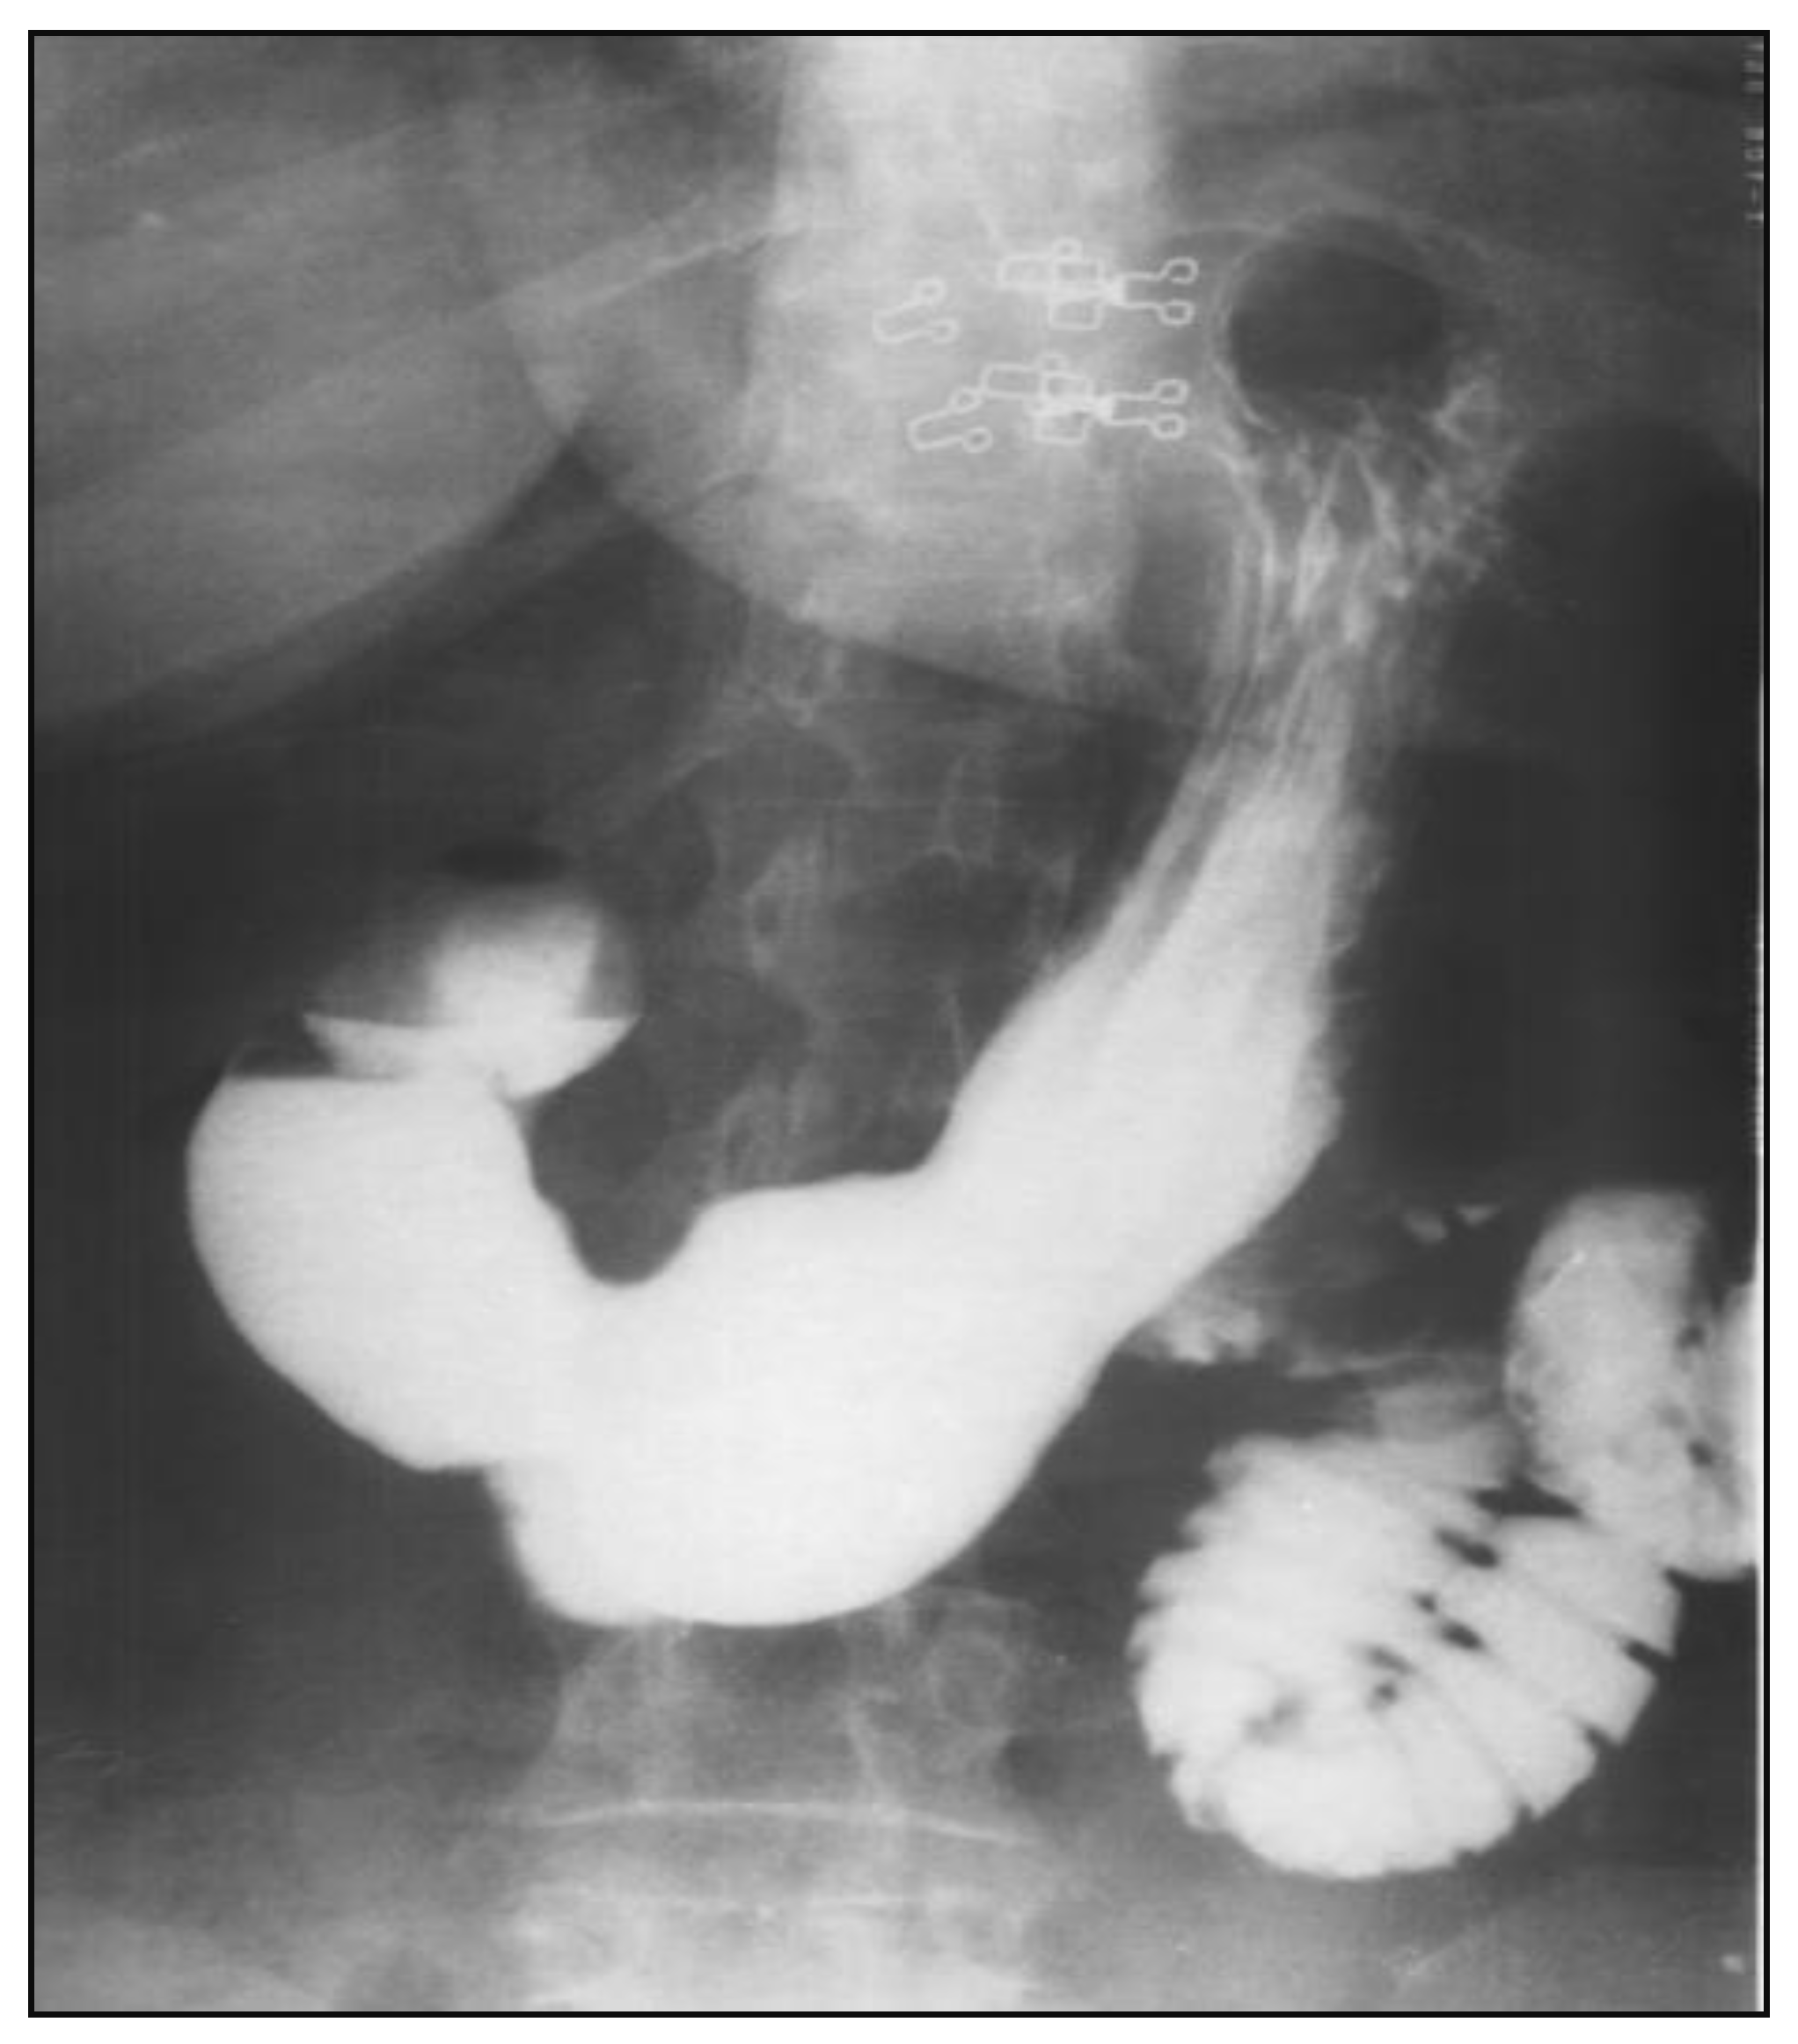

The patient is disease-free after a 1.5 year follow-up. A recent barium gastrointestinal follow up study demonstrated a widely patent anastomosis with a normal mucosal pattern between the proximal duodenum and jejunum (Figure 7) and ultrasoudsonography and CT scan do not highlight pathological lesions.

Figure 7. Follow-up barium study of the upper gastrointestinal tract widely patent anastomosis with a normal mucosal pattern between the proximal duodenum and jejunum.